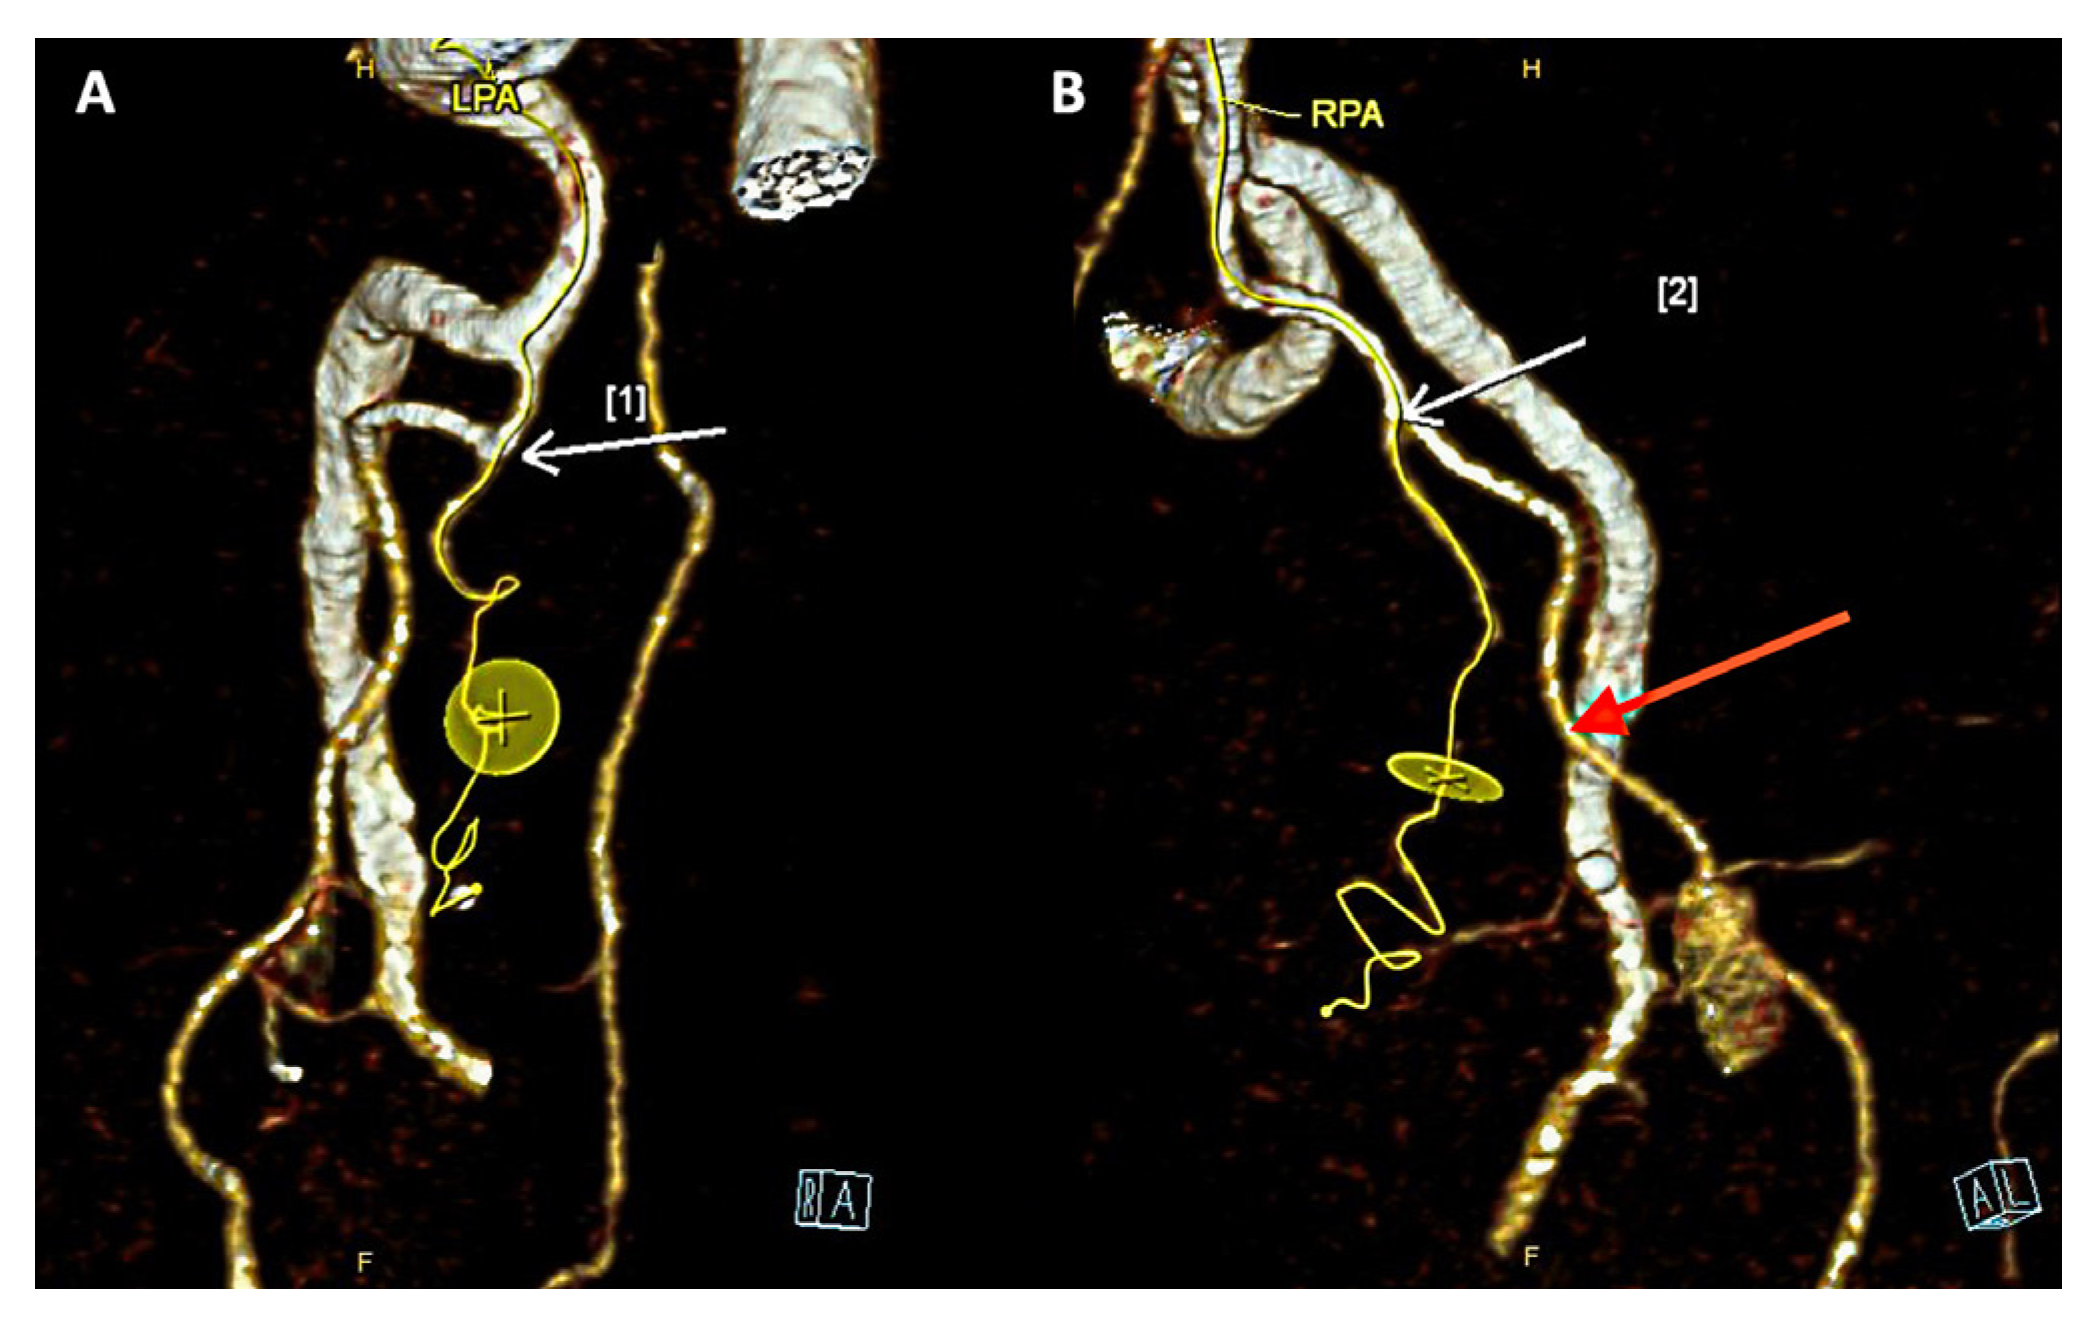

Figure 3.

Three-dimensional reconstructions of a pelvic angiogram of a 77-year-old patient (case 3) undergoing prostatic artery embolization revealing selective catheterization of the left and right prostatic arteries (LPA & RPA – white arrows). (A) The left prostatic artery originated from the middle rectal artery; (B) The right prostatic artery was identified to originate from an accessory pudendal artery (red arrow) which is also seen supplying the penis.